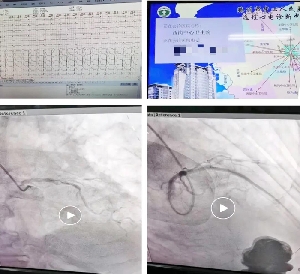

完美配合 只為初“心”——我院胸痛中心成功救治1例急性心肌梗死···

9月23日9:30分,西崗中心衛(wèi)生院通過遠程心電網(wǎng)絡發(fā)現(xiàn)一例急性緊急梗死患者,胸痛中心聽班電話聯(lián)系網(wǎng)絡醫(yī)院醫(yī)生及患者家屬,并與患者家屬溝通后,啟動胸痛中心綠色通道,120救護車“雙繞”導管室,10:40分于前降支成功植入支架1枚,門球時間30分鐘,患者安返監(jiān)護病房進一步救治。自我院創(chuàng)建胸痛中心以來,對胸痛患者的識別